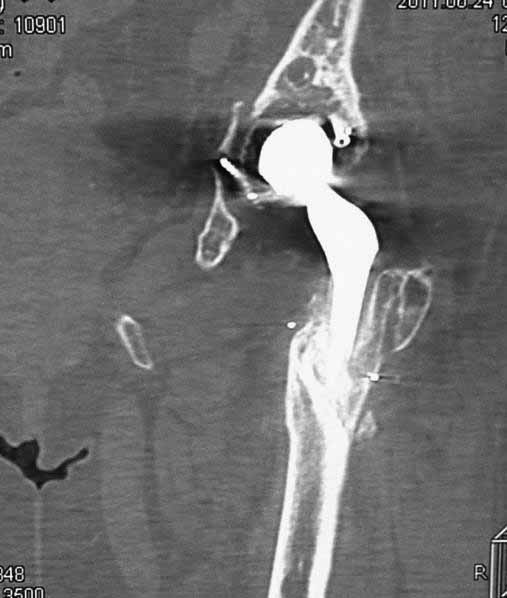

Уважаемые коллеги. Хотелось бы услышать мнения и советы по представляемому случаю. Пациентка 45 лет. Бесцементное эндопротезирование левого тазобедренного сустава 6 лет назад (впадина RM, Mathys, металл-металл, ножка Зульцеровская). За 10 лет до протезирования – коррегирующая остеотомия бедренной кости, которая не срослась в течение года до удаления пластины, а затем срослась в течение 3 месяцев иммобилизации в кокситной повязке. После протезирования получилось наблюдать пациентку почти постоянно, поскольку через 2 года синтезировал ей лодыжки на оперированной стороне, затем, через несколько месяцев удалил фиксаторы, а в 2009г. резецировал мениск на противоположной стороне. Боли все эти годы не беспокоили. Пациентка чуть выше среднего роста, вес тела нормальный. Физические нагрузки переносила хорошо. Работает на 7 этаже без лифта. Год назад экстирпация матки по поводу лейомиомы больших размеров. Несколько месяцев назад появились боли в области левого тазобедренного сустава. При рентгеновском и КТ исследованиях (июль с.г.) – нестабильность тазового компонента. От предложенной замены протеза пациентка на тот момент, слава богу, отказалась. Через какое то время боли в области левого тазобедренного сустава практически полностью прошли, а около 2 месяцев назад появилось ощущение патологической подвижности таза и боли в паху справа, которые через некоторое время уменьшились, а потом снова усилились после значительных физических нагрузок (много ходила по песку на пляже, носила тяжести). Ежедневно принимала диклофенак. На рентгенограммах – переломы правой лонной кости. Сейчас госпитализирована из-за болей в паху справа. Боли слева не беспокоят. На фоне снижения нагрузок в стационаре боли значимо уменьшились. Способна ходить без средств дополнительной опоры.В анализах крови чуть повышены трансаминазы и гамма-ГТ, моча без особенностей.

Вопросы: -правильно ли я расцениваю переломы как стрессовые на фоне неполноценного таза (pelvic insufficiency stress fractures)? -Можно ли так же расценить ситуацию на стороне протеза и, соответственно, не торопиться с ревизией, рассчитывая на вторичную стабилизацию? Уж больно не хочется менять ножку. -Если думать о ревизии, то когда? На представленных снимках тазобедренный сустав до и сразу после операции, затем 2 снимка 2009г., когда ничего не беспокоило, затем КТ 2-х месячной давности и вчерашние рентгенограммы обоих тазобедренных суставов.

Сергей, очень возможно, что перелом и стрессовый, но мне видится, что его причина в нестабильности чашки. Дело в том, что в отличии от ножек, чашка при своей дестабилизации болит гораздо меньше и больные терпят до последнего.

При сравнении рентгенограмм можно увидеть насколько чашка переместилась от места своего первичного расположения. От опрокидывания ее удерживают конструкционные элементы "рожки". Без них ситуация, возможно, уже была бы катастрофической (чашка в тазу). Думаю надежды на вторичную интеграцию, могут быть обмануты и ревизии не избежать.